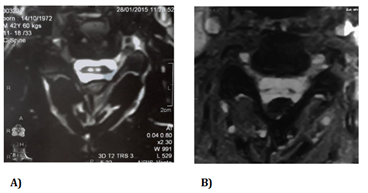

The first practitioner thought to peripheral nerve disorders and asked a lumbar scan and ENMG. The lumbar Scan performed showed degenerative osteoarthritis of the hinge lumbar without disco radicular conflict. ENMG was normal but Evoked Somesthesic Potential (PES) showed right S1 radiculopathy. After one month of unsuccessful treatments, the first cervical MRI is performed and showed one T2-weighted sagittal midline image with elevated signal within the cord at the C3-C4 level over a length of 30mm with the loss of cord volume. The T2-weighted axial image at the level of C3 demonstrates bilaterally symmetric well-circumscribed circular shaped foci with increased signal intensity. The appearance approximates the shape of a snake's eyes (Figures 1–3).

Figure 3 T2-weighted axial image at the level of C3 demonstrates bilaterally symmetric well-circumscribed circular shaped foci of increased signal intensity. The appearance approximates the shape of a snake's eyes.

A) 2015 spinal cord MRI -B) 2017 spinal cord MRI.

He comes to neurology consultation in october 2017, given the persistence of pains and deficit despite the analgesic and anti-inflammatory treatments associated with physiotherapy. Clinical neurological examination shows a walking by mowing with the right lower limb. Non-proportional right hemiparesis more important on the lower limb. Bilateral hyperreflexia with bilateral Babinski and Hoffman signs, bilateral amyotrophy of the proximal muscles, tactile hypoesthesia in the right hemibody, algesic hypoesthesia in the left hemibody, no vibration and position sense perception, a sensory ataxia and no cranial nerves disorders. The new spinal cord MRI performed in 2017 shows the same images in cervical level with more atrophy (Figures 1–3). Brain MRI is normal. The blood cell count shows WBC:4, 2g/L, Hemoglobin:13,9g/100ml, MCV:92μ3, Platelet:264g/l ; Blood erythrocyte sedimentation rate (1H):4mm; C-Reactive protein:0,4mg/l; Negatif human immuno-deficiency virus test.

based on MRI alone. Sagittal MR images of anterior spinal artery infarction usually demonstrate an isolated pencil-like area of T2-hyperintensity involving the centromedullary region, often encompassing more than 2 vertebral segments.3,6 Because of the higher vulnerability of the gray matter to ischemia, axial T2-sequences may show bilateral hyperintensities that are mostly confined to the anterior horn area, leading to the typical snake eyes or owl’s eyes configuration.6,7 In the chronic stages, localized atrophy is possible,1 like in this case study, making it difficult to accurately locate hyperintensities in the anterior horn area in axial T2-sequences.